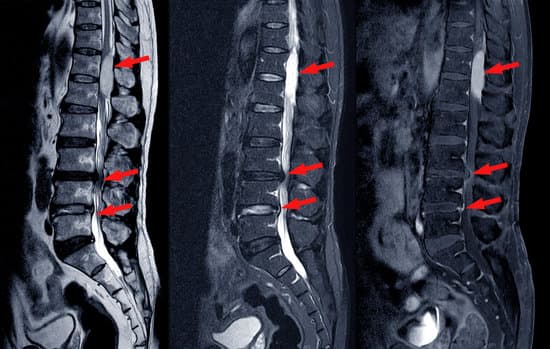

척추관 협착증을 진단하기 위해서는 의사와의 상세한 병력 청취, 신체 검사, 그리고 필요한 경우 영상 진단 검사가 포함됩니다.

정확한 진단은 적절한 치료 계획을 세우는 데 중요한 역할을 합니다.

영상 진단 검사

자기공명영상(MRI): 척추 주변의 연조직, 신경, 인대 등을 세밀하게 확인할 수 있으며, 신경 압박의 정도와 위치를 파악하는 데 매우 유용합니다.